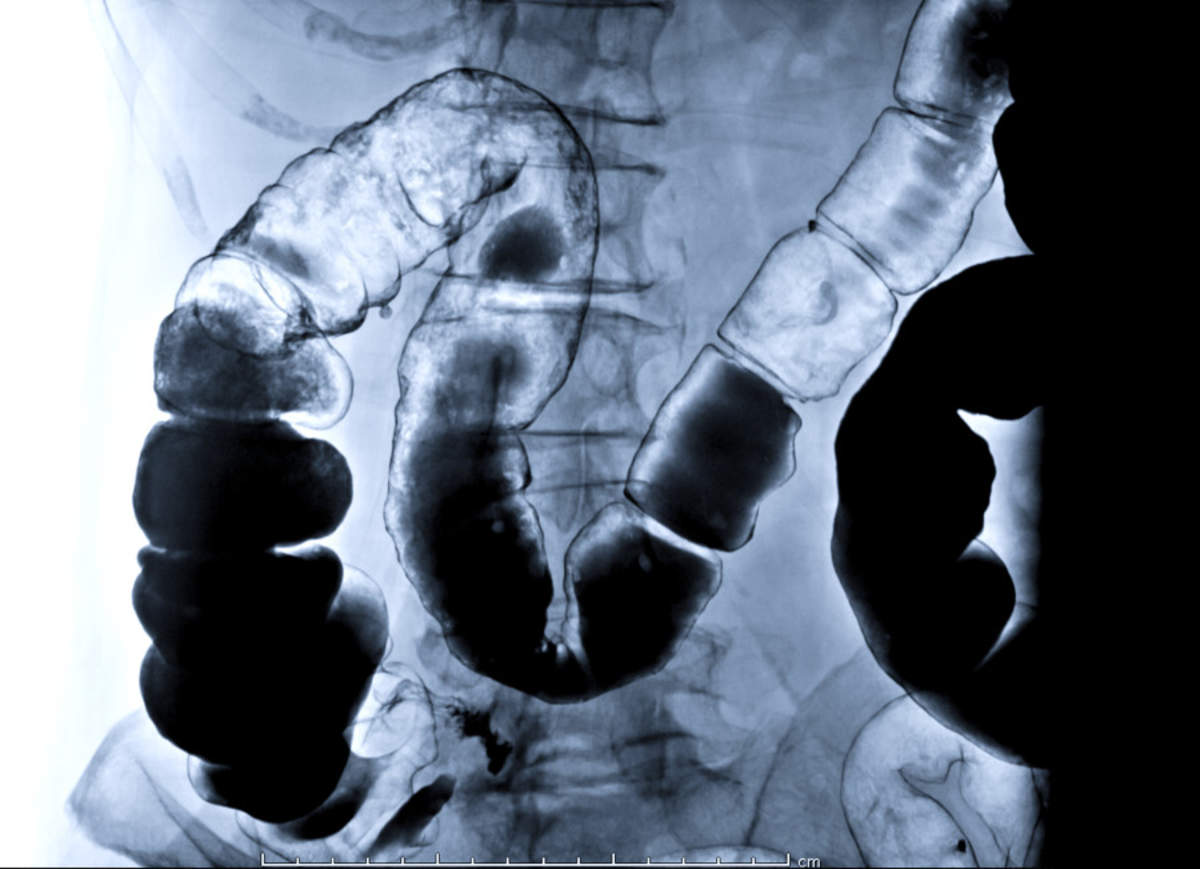

tests for crohn's disease Enema barium rectal colon rectum coats crohn bowel inflammatory fluoroscopic obtained divertikulose apendice replacing

enema barium rectal colon rectum coats crohn bowel inflammatory fluoroscopic obtained divertikulose apendice replacing